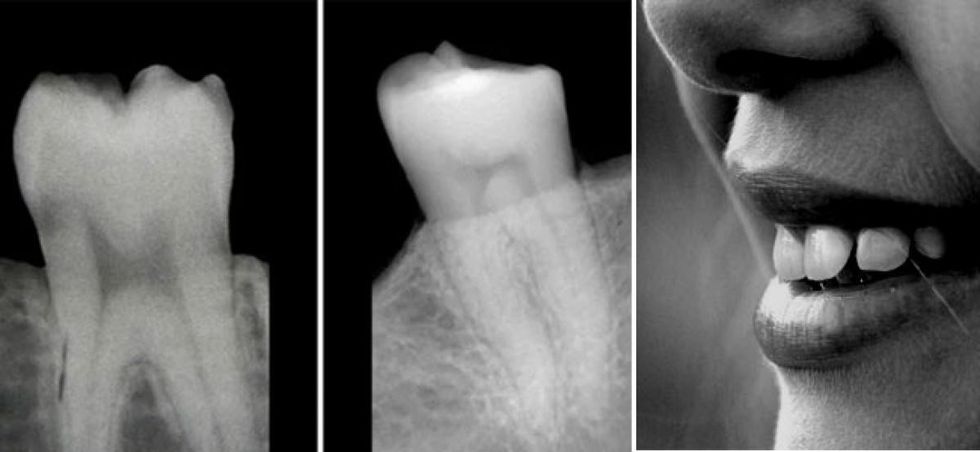

Shumë pacientë të cilët kanë një higjienë të mirë orale dhe tek të cilët nuk kemi predispozita gjenetike për zhvillim të parodontopatisë, por edhe që nuk janë diagnostikuar me ndonjë sëmundje sistemike (sëmundje të gjëndrës tiroide, sëmundje të gjakut, etj.), por që kanë humbje të masës kockore (ashtërore) në të dy nofullat, atëherë duhet analizuar vlerat e vitaminës D.

Dallimi mes strukturës së shëndoshë të dhëmbëve dhe dëmtimi i strukturës së tyre nga mungesa e vitaminës D

▪ Kockat e të dy nofullave resorbohen (zvogëlohen - harxhohen), gjë që mund të sjell deri te humbja e dhëmbëve.